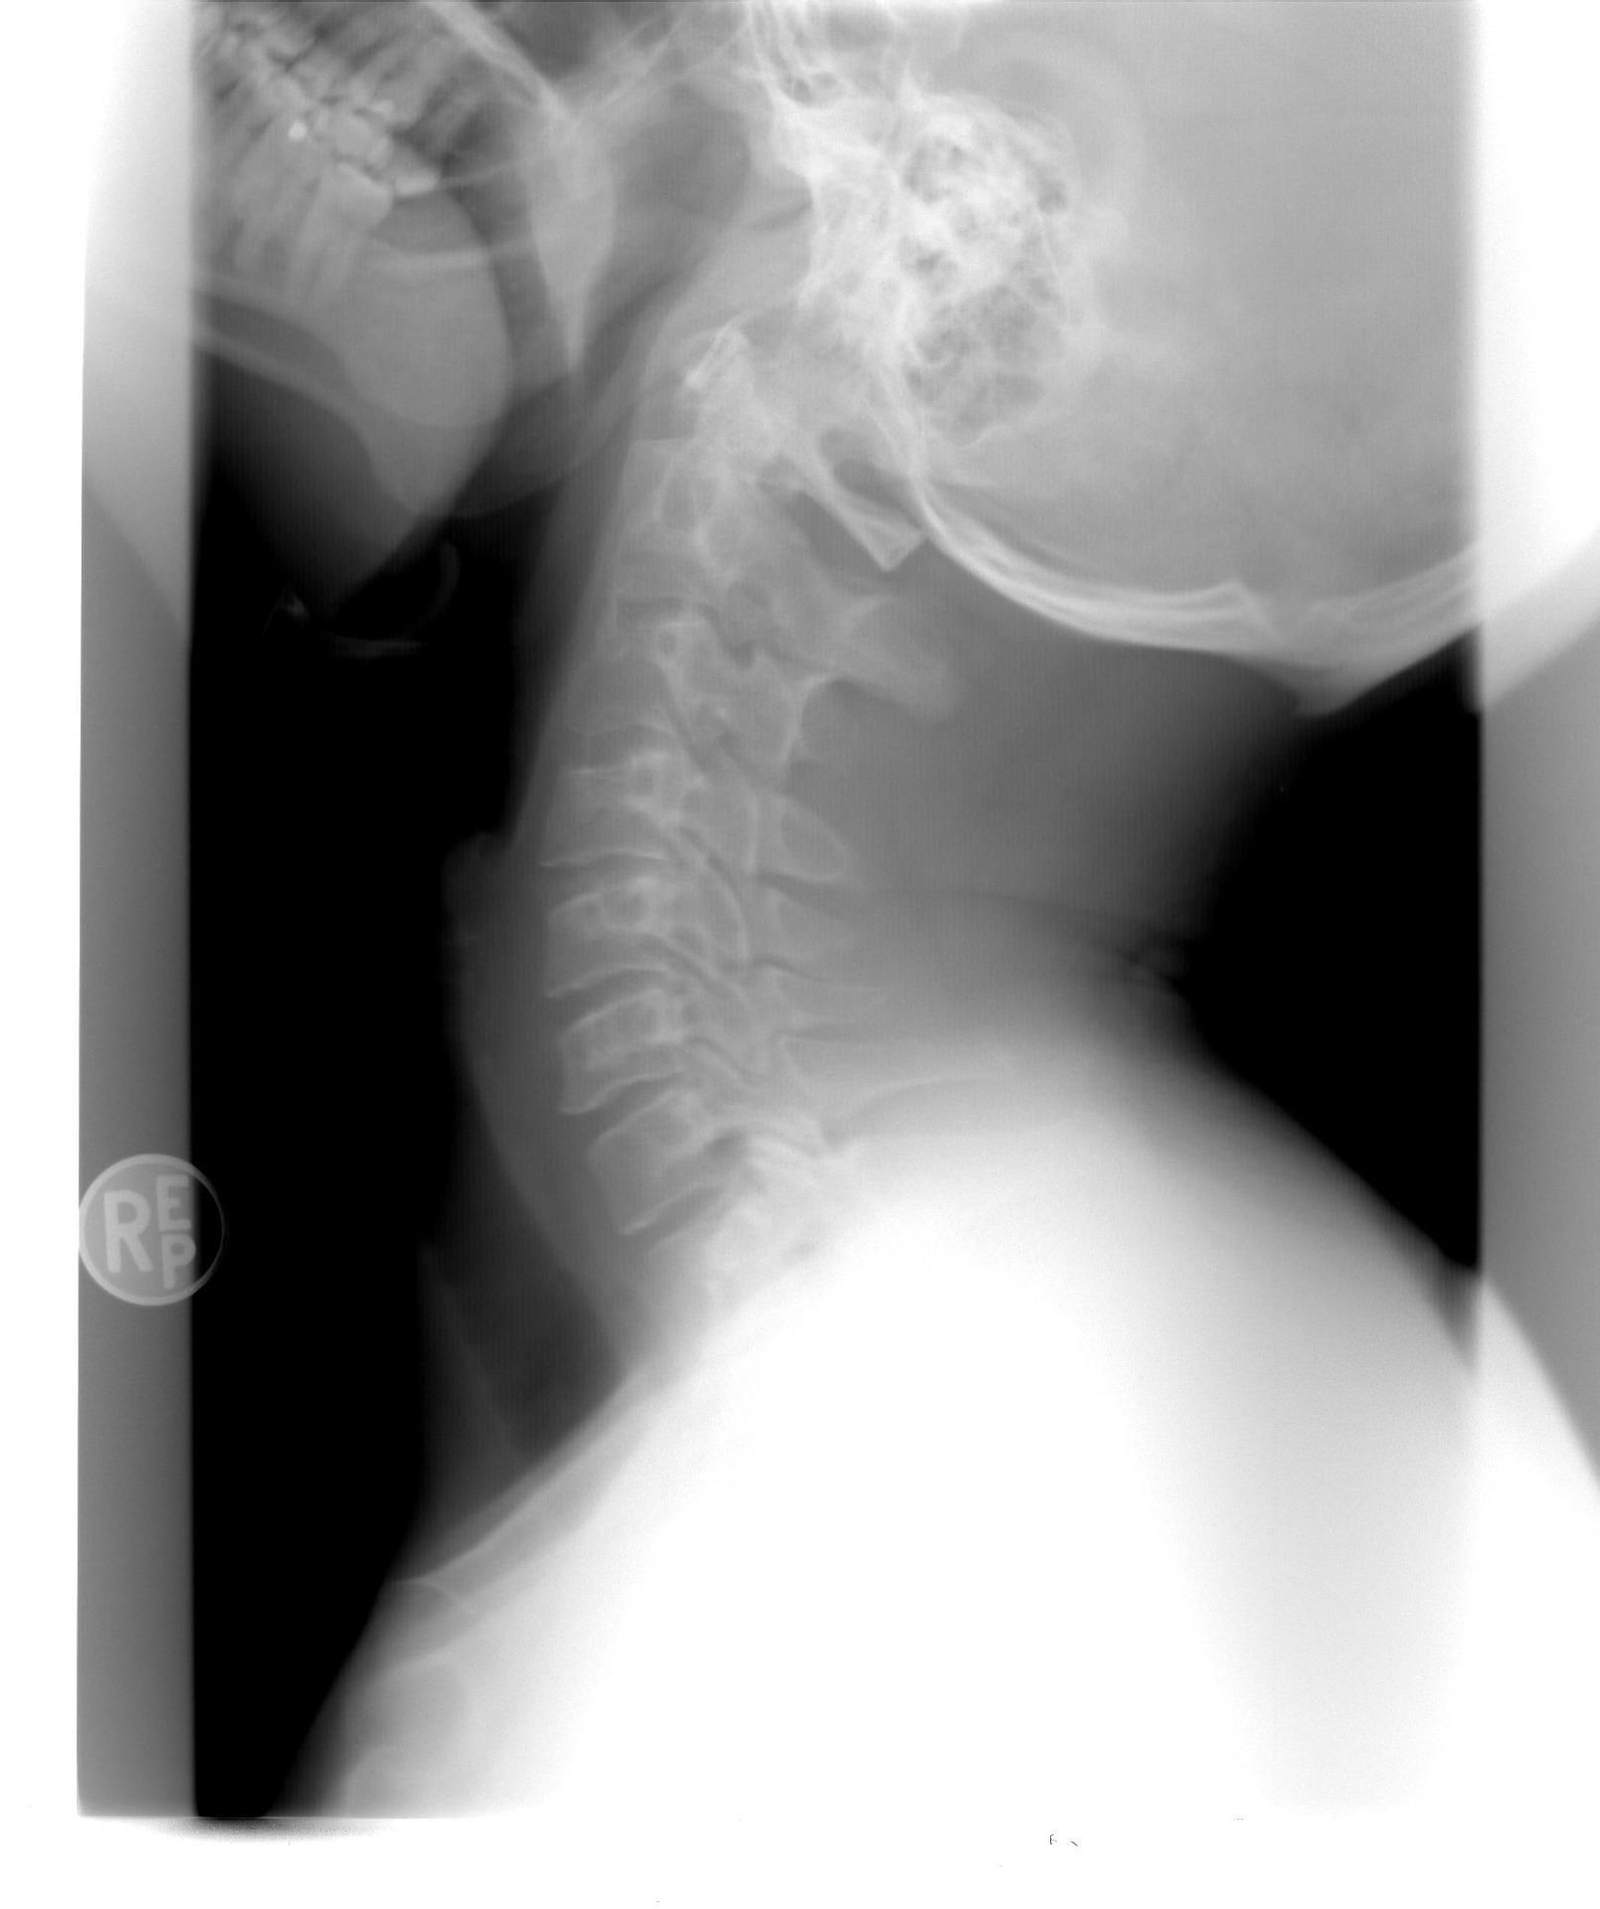

Radiografía

Radiografía / D.A.

El 90% de las cervicalgias son debidas a procesos degeneraticos o mecánicos, se dividen en dos grandes grupos, (1) las originadas por afectación articular y/o tensión muscular/fascial (2) las que afectan a las raíces nerviosas o médula espinal. Solo el 10% se deben a enfermedades potencialmente graves como un tumor o infección. Aproximadamente entre el 14-20% pueden llegar a cronificarse. De nuevo la revista Spine considera la cervicalgia un importante problema de salud con altas repercusiones económicas y sociales.

De manera general podemos hablar de tres causas principales, en primer lugar tenemos las de tipo traumático, en segundo lugar las de tipo mio-conjuntivo debidas a sobrecargas y esfuerzos mantenidos y repetitivos. Si esta situación se mantiene en el tiempo se genera un aumento importante de “puntos gatillo” y compresión en los discos intervertebrales con posibilidad de protusión y hernia discal. Finalmente, en tercer lugar tenemos las de tipo nervioso por pinzamiento del nervio o estenosis (estrechamiento) del canal medular debidas a enfermedades degenerativas, artrosis o el mismo proceso de envejecimiento. Las de tipo nervioso puede ser consecuencia de traumatismos directos sobre la zona cervical y por tensión miofascial crónica.